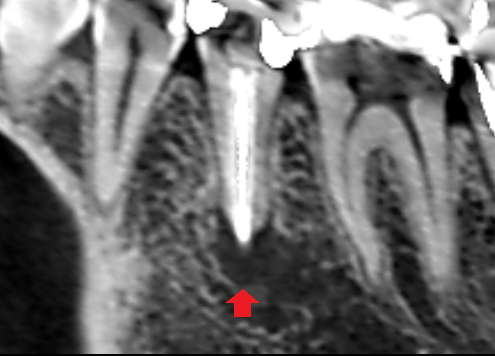

下顎第二小臼歯の初診時の冠状断のCT画像です。

赤い矢印の先に膿の影がみられます。膿は、画像では右側の舌側で拡がっていました。